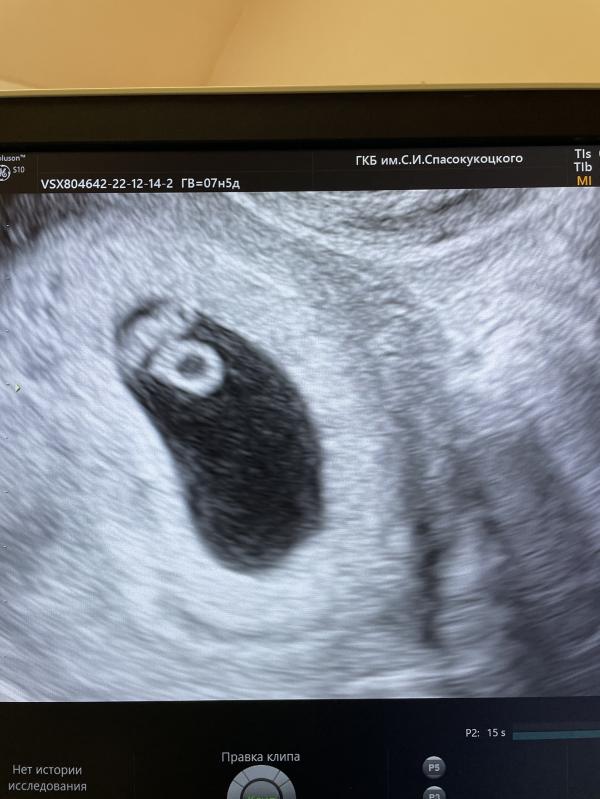

Первое узи 🥰♥️

14.12.2022